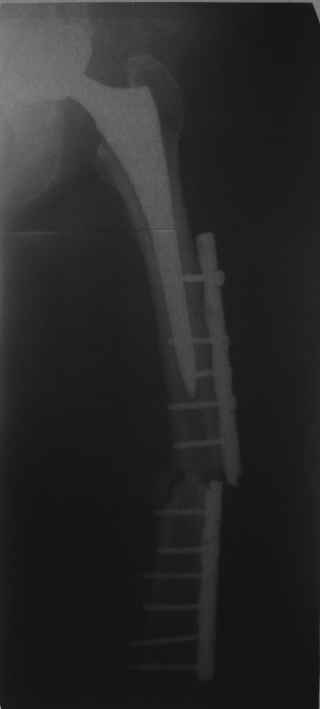

Обещанные ранее снимки Заранее спасибо.

Это сплошной титановый стержень. На дистальном конце отверстия под кондуктор. На другом - канал под ножку глубиной 60 мм, стенки толщиной 2,5-3 мм. И там же продольный пропил, чтобы канал мог адаптироваться к ножке.

Сейчас опорную нагрузку на бедро берет на себя система от бедренного компонента эндопротеза до проксимального винта в интрамедуллярном гвозде. Свидетельство тому - реакция кортикала утолщением вокруг того самого винта. Таким образом вся кость от верхушки б.вертела до проксимального винта не испытывает физиологической осевой нагрузки. Результатом этого могут стать следующие последствия друг друга не исключающие: 1) все будет хорошо до перелома опорной системы по винту(ам) или в месте соединения штифта с ножкой или еще где-либо, 2) исключенная из-под нагрузки кость будет терять в количестве и качестве, что не очень (или очень не) хорошо для возможных будущих ревизий (тьфу-тьфу!!!).

О качестве сращения перелома тоже сказать трудно. Выраженной мозоли нет. В боковой проекции отломки накладываются друг на друга. В прямой проекции зона перелома в наружной части закрылась не полностью. Возможно причина тому - недогрузка кости.